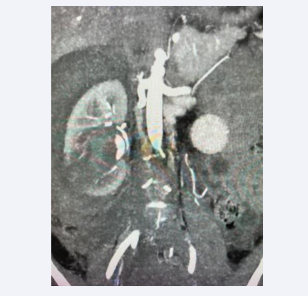

Subsequently, CT angiogram confirmed a ruptured pseudo aneurysm with intra renal and intra- capsular haematoma (Figure 3).

CT angiogram.

Figure 3: CT angiogram.